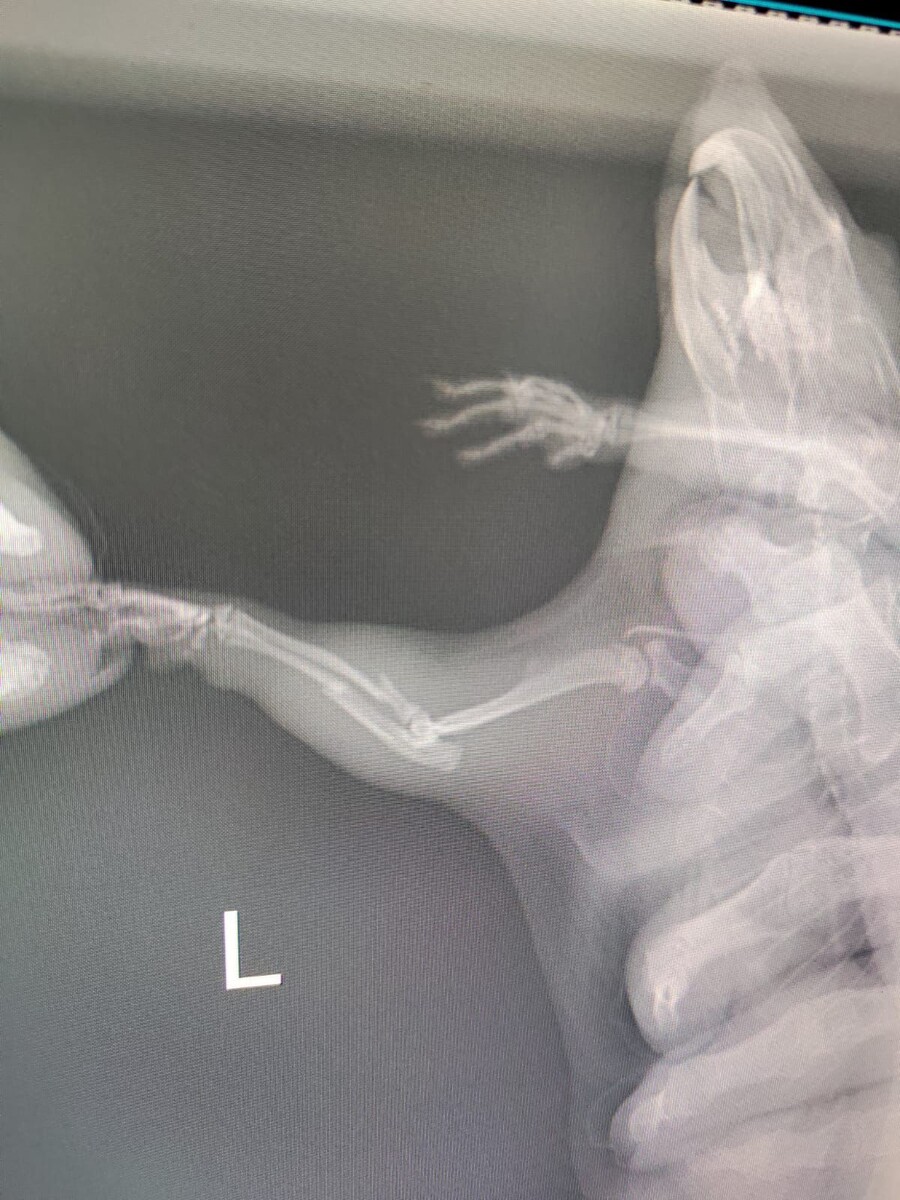

Годовалый малыш Крыс с жалобой на подгибание и отёк левой грудной конечности

На приём обратился годовалый малыш Крыс с жалобой на подгибание и отёк левой грудной конечности, выполнена рентгенография - косой перелом со смещением локтевой и лучевой кости , проведено обезболивание, даны дальнейшие рекомендации